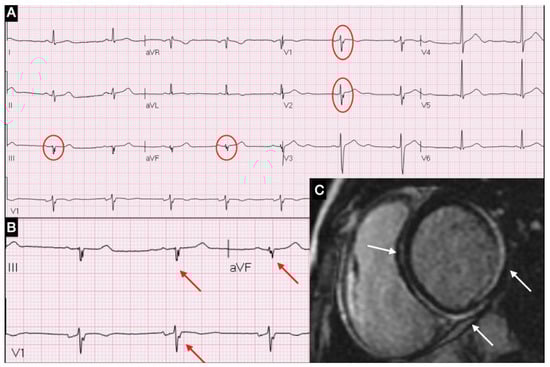

The belief in the lack of specificity of the ECG has been recently challenged by recent data suggesting that fQRS might be a new additional specific sign correlating with the presence and topographic distribution of myocardial inflammation (Figure 1) [21,22].

Figure 1. (A) ECG showing fQRA in leads V1, V2, DIII and aVF; (B) Magnification of fQRS; (C) CMR short-axis view with LGE in inferior-lateral and septal areas.

Evidence of QRS fragmentation occurred with a latency of 3 (2–6) days from the onset of symptoms. ECG leads showed that fQRS matched the myocardial area of the LGE distribution in 38 patients (95%) (Table 3).